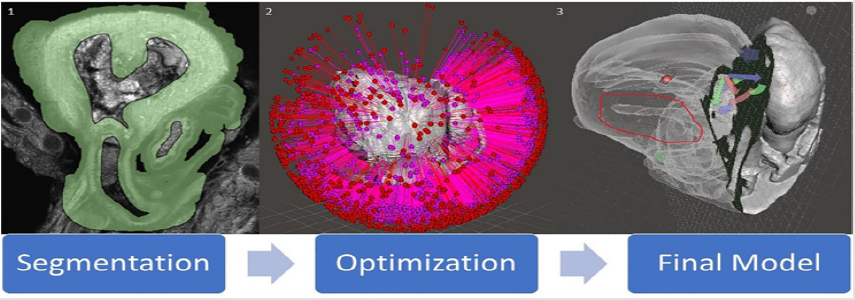

Two open source software programs were used to establish this pipeline and a workflow established. Horos 33, a 3D segmentation, visualization, and reconstruction software; and Meshmixer 34, a 3D model editing software, were used in this project develop the model. A method in Horos was developed to overcome the difference in textures between human and preclinical imaging modalities, ultimately resulting in a 3D surface rendering of genetic mouse model heart and brain defects. Meshmixer was then used to edit said models to correct file sizes and prepare models for 3D printing. Here we outline the work flow for 3D imaging processing of 3D modeling for micro-CT, micro-MRI, and ECM for 3D printing into three steps: (1) segmentation, (2) surface rendering, and (3) optimization (Figure 4). Each step is essential to creating a final product, being a 3D printed model that accurately displays the phenotype of a given genetic mouse model, that can then be used to gain a deeper understanding of defects present in genetic models.

Segmentation

Segmentation (Figure 4) is to be carried out in the Horos software and is arguably the most important step of the process with regards to creating an accurate model. It is also where the largest deviation from human and preclinical modality conversion methods manifests. Human modalities have a much better contrast present than that of preclinical modalities, hence the segmentation process is more complicated. Instead of just thresholding and using simple tools to select regions, unwanted areas need to be cropped out by the segmentor. Essentially, it is more difficult to signify to the computer which pixels in the image stack are to be converted into a model (tissue) and which pixels are to be left out (grey space and cavities) and so extra measures must be taken. Hence, a process for segmentation and conversion was developed for ECM data. The ECM scan data which is in .tiff format is loaded into the Horos software using the import data function in Horos. This automatically loads the data in three planes. Interpolation, cropping, and thresholding were used to achieve accurate segmentation in this process. This segmentation process can be ordered into three different steps

Figure 4: A diagram of the conversion process for ECM modality. (1) is a screenshot of one segmented image from a .tiff image stack. (2) is an unoptimized model immediately post surface rendering highlighting how many errors can be present in a model. (3) is a final optimized model with slicing to show internal cavities and exterior. The region of the image circled in red shows the HLHS deformity in the model. Versatility of slicing can be seen through the arrows present on the image, showing that the plane slicing the model can be easily moved in any direction.

Surface Rendering

Surface rendering (Figure 5) is to be carried out in Horos post segmentation. It can be initiated through the surface rendering tool in the Horos software. Upon initiating the software, a window will appear asking for pixel value. A pixel value of 3024 should be entered into the box as all relevant segmentation regions should now have a pixel value of 3024 as per the previous step. The segmentations are assembled together by the program and a 3D mesh is created. If there are any holes present in the segmentation, a surface rendering will still be created, however will not be printable. Simple examination of the model created should show if it is sufficient to proceed. If it looks destroyed and incorrect, segmentation needs to be re-checked. Once this task is complete, the software will output a file in the filetype of .stl which is then compatible with 3D editing software.

Optimization

Upon rendering and exporting a .stl filetype, the model can be opened in the Meshmixer software. Optimizing the model (Figure 4) reduces file size by removing countless overlaps in data and unneeded pixels stemming from the original image stack that manifest in the mesh. Here, tools are available to repair holes in the mesh, fix overlapping edges in the data, and make it compatible with printing. This step is integral to printing because without it, the print would most likely fail if it would print at all. The tools that were used in this process were